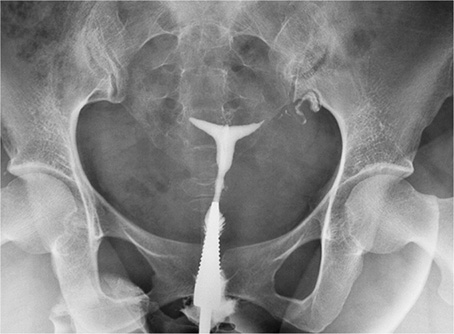

A Bilateral Cornual Block Before Treatment B Patent Bilateral